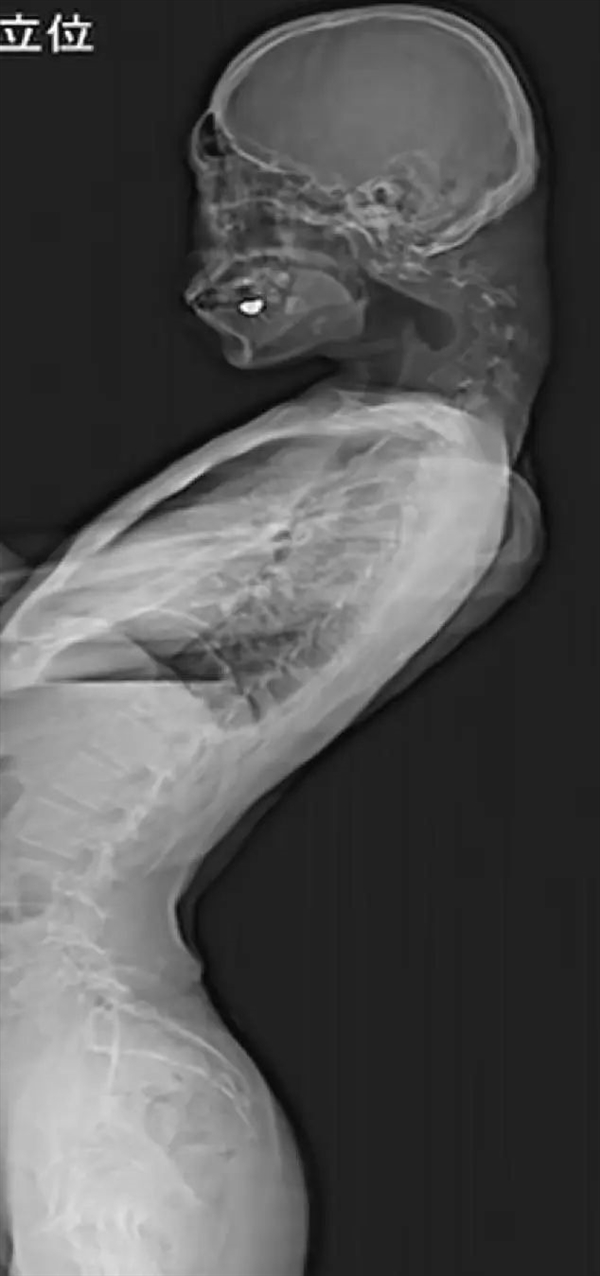

可以看一下上面这张图片:他的后脖子那里长了一个“角”,颈椎过度弯曲,几乎呈“对折”的状态,而且头软弱无力,也抬不起来,直接支撑在胸口上。

这种症状,就是所谓的“垂头综合症”。

由于长期保持低头姿势,颈椎骨长时间保持“极度拉伸”状态。到2023年,他的颈椎严重变形、脱臼,颈后出现了一个类似于角的肿块,头就直不起来了。

到医院后,男子的头完全耷拉下来,贴在自己的胸前,医生决定先用颈托来矫正,但男子反馈使用颈托后,颈部会麻木,不舒服,最后医生不得不进行手术治疗。

手术中,切除了部分受损椎骨和疤痕组织,然后植入钉子和金属来稳定颈部,以达到“强行”矫正颈部的目的。